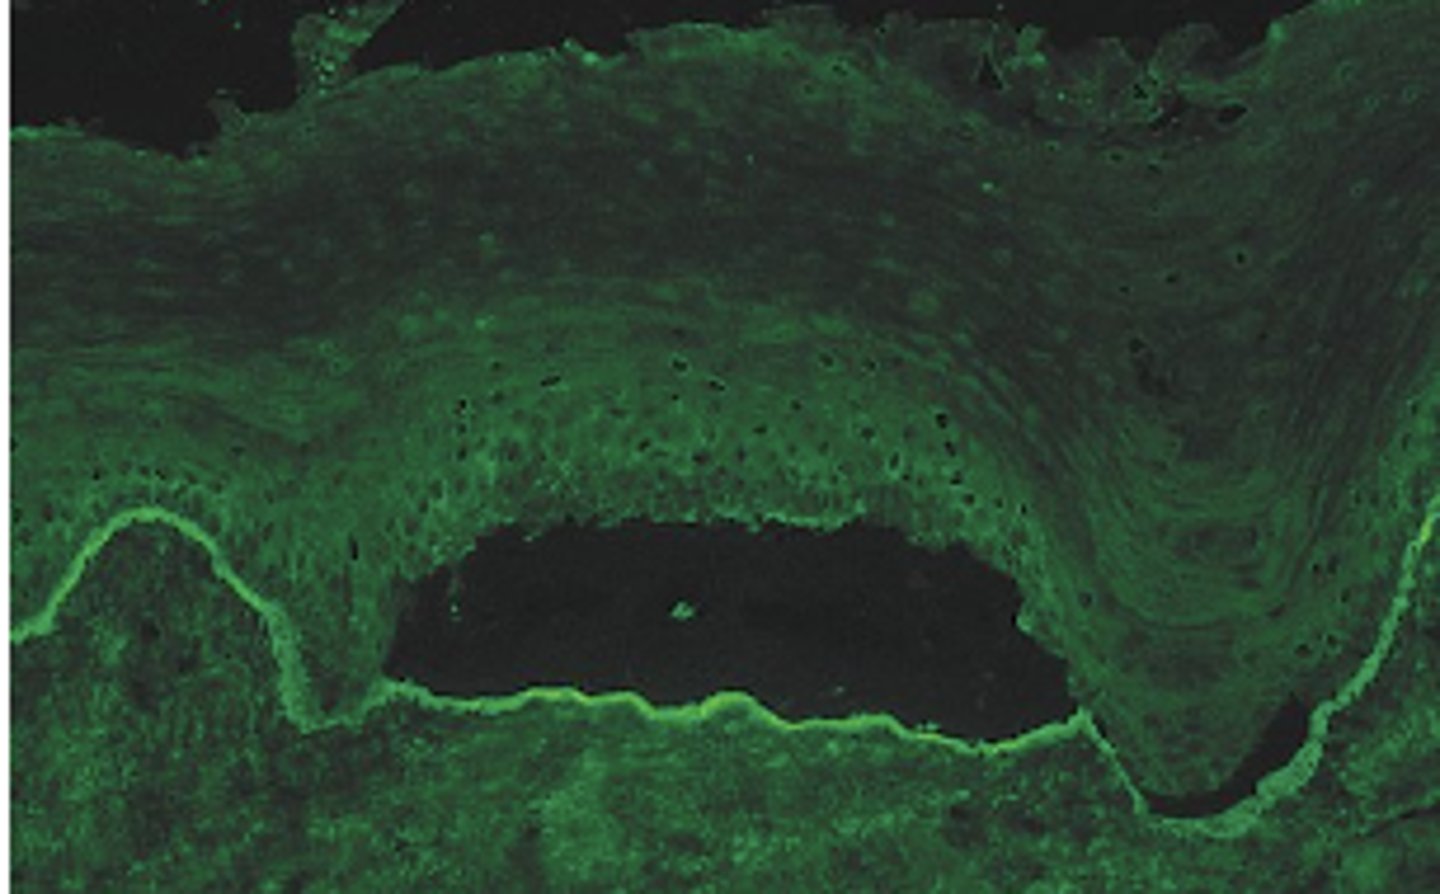

Blistering in this disease is due to antibodies directed against component of ___? (picture showing histo slide with intraepithelial split)

What cell layer is affected in pemphgUs (PICTURE ON DRIVE)?

Blistering in this disease is due to antibodies directed against component of ___? (picture showing histo slide with basement layer split)